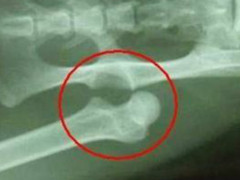

据悉,今年9岁的王雪凌是白沙县元门小学的学生,去年11月,她在玩耍时手臂摔伤,年幼的她因害怕被父母打骂而一直没敢跟家长说,而其父母那段时间也因闹离婚而对孩子的伤情浑然不知,小雪凌就这样默默地独自忍受着痛苦。直到3个月后,父亲王进强才发现女儿的手臂变形了,但他依然没有意识到问题的重要性,只是给孩子敷了点草药。

过了一段时间,王雪凌手臂开始流脓,并且有苍蝇围着她乱飞,此时,王进强才觉得严重,慌忙将女儿送往县医院治疗,医生建议他到海口的大医院去治。海口的医生说,王雪凌已经错过了最佳的治疗时机,而且病情还在不断的恶化,现在面临截肢,大笔的医疗费已经将王进强逼至崩溃的边缘。